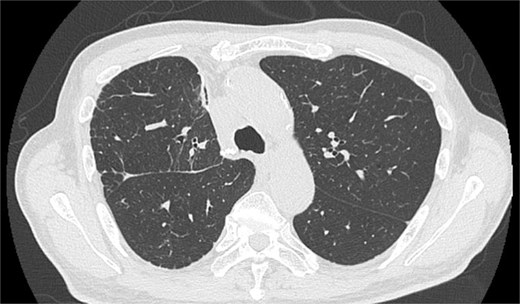

On POD 6, SE developed and spread to the chest, neck, and face. CT demonstrated remarkable mediastinal and SE with minimal lung collapse (Fig. 2; Video 2). Therefore, a chest tube was inserted, but minimal AL occurred from the chest tube, and the emphysema worsened. On POD 11, we performed thoracoscopic exploration and therapeutic intervention. Dense adhesion was confirmed between the staples on the interlobular plane and the dissected upper mediastinum. These were released, revealing the previous pleural tear. No other causative factors were observed. CT and operative findings suggested late-onset AL into the dissected mediastinum through dense adhesions. A leak test under positive pressure of up to 20 cmH2O revealed no AL from the pleural tear. The tear was sealed using a PGA sheet and fibrin glue, and 130 ml of autologous blood was injected into the pleural space to seal the dissected mediastinum and prevent air inflow (Video 3).

After the reoperation, AL was not observed, and SE regressed. The chest tube was removed on POD 5 after the reoperation (POD 16 after initial surgery). The patient was discharged on POD 18 after initial surgery. CT performed after 1 year revealed no emphysema or cancer recurrence (Fig. 3). The patient was informed of the complications and accepted the treatment outcomes.